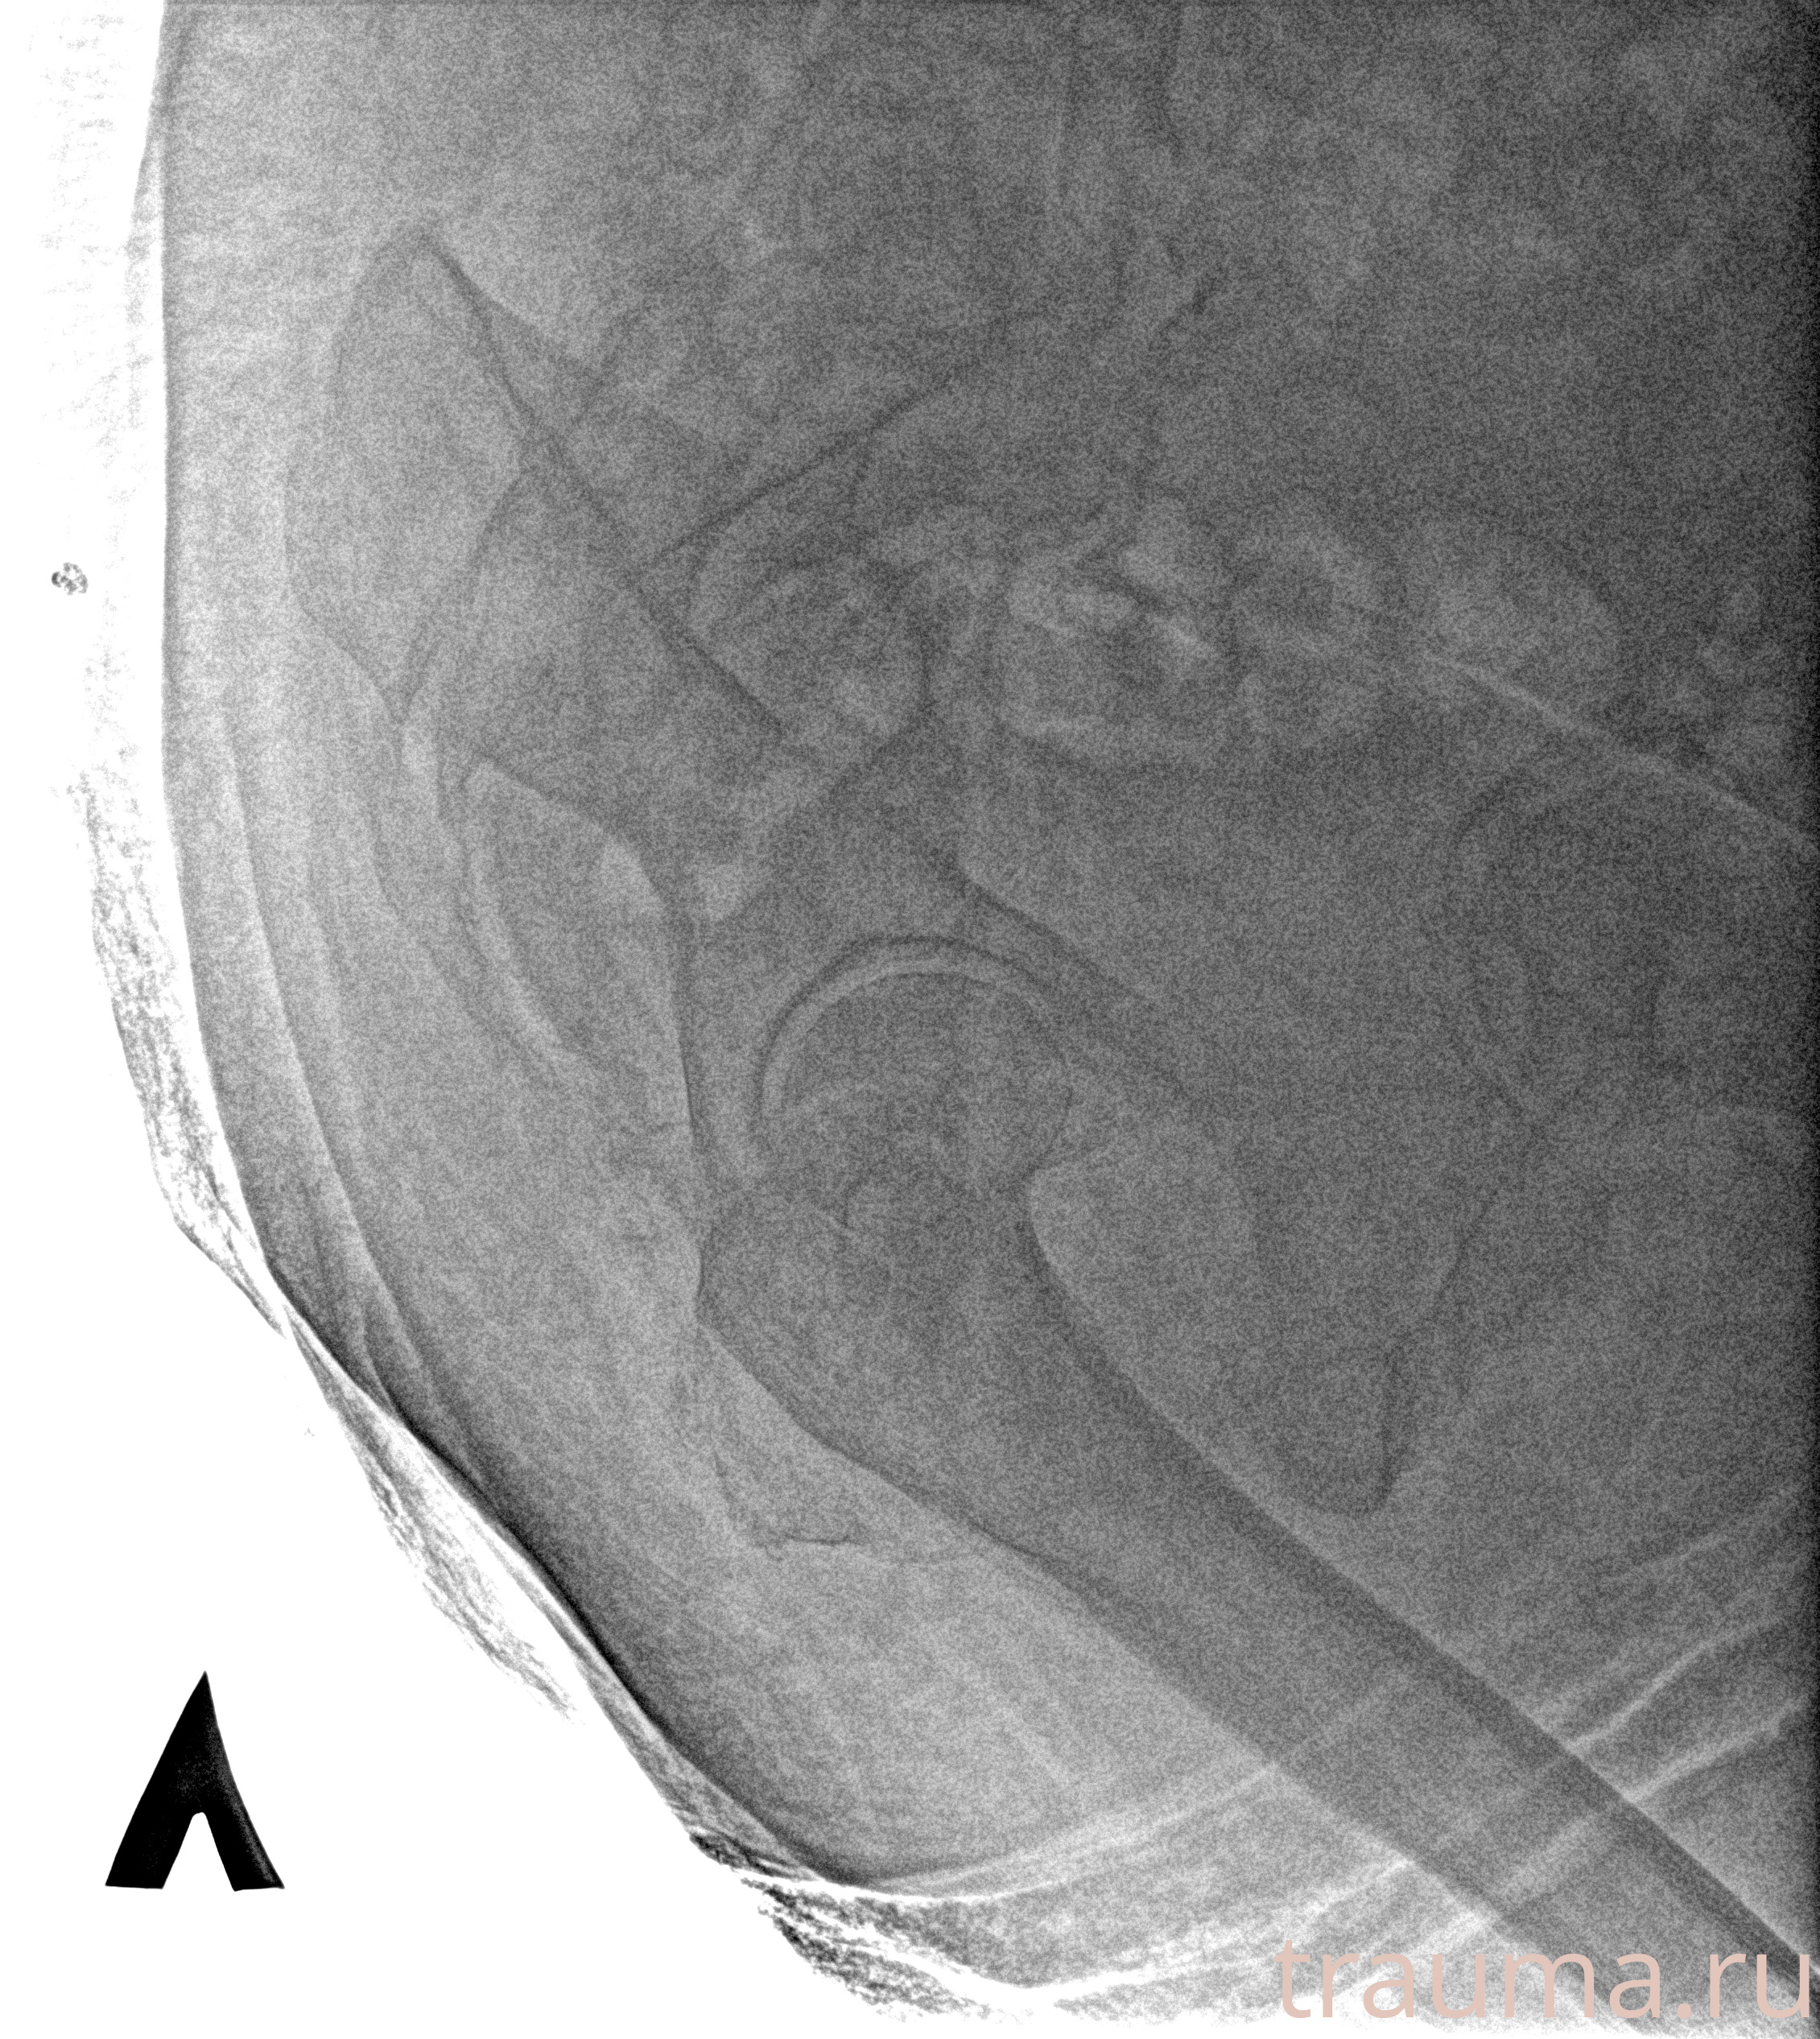

Рентгенограммы

Рентген на дому: по вашему адресу приезжает врач-рентгенолог, травматолог-ортопед с мобильным рентгеновским аппаратом, проводит диагностику травмы или заболевания, делает необходимые рентгенограммы, дает рекомендации по дальнейшему лечению. Получить качественные снимки в домашних условиях возможно благодаря уникальной методике, разработанной МосРентген Центром для института  Склифосовского